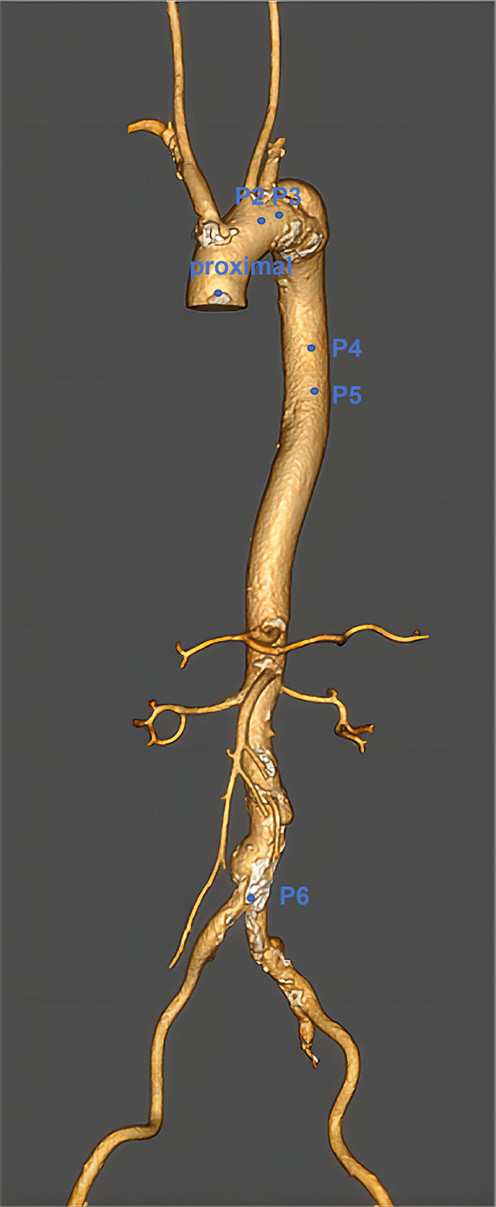

Inclusion criteria: 1. Patients presented with clinical symptoms of aortic arch disease, such as chest pain and tightness. 2. Aortic arch disease was confirmed using computed tomography angiography (CTA) (Figure 2). 3. Patients met the Castor stent graft indications: presence of aortic arch disease with proximal lesions situated 15 mm distally to the left common carotid artery (LCCA) and 20 mm distally to the LSA, with extension into the LSA and a proximal landing zone of at least 15 mm.

Guidewire and stent placement: After establishing vascular access from the left brachial artery to the right femoral artery, a transverse incision was made in the right inguinal region, and the femoral artery was dissected. The selected Castor stent graft was then inserted through the right femoral artery, with placement guided by real-time imaging. The direction-turnover technique was utilized to ensure that the stent fenestration aligned precisely with the aortic arch branches, with the stent automatically flipping to the correct position upon advancement. Re-angiography confirmed the positioning of the stent, showing unobstructed branch arteries and complete lesion coverage (Figure 3).

Variables

The primary outcomes measured included: Operation time: Defined as the time from brachial artery puncture to the removal of all guidewires and catheters. Blood loss: Amount of blood lost during surgery. Complications: Including residual shunt, arrhythmia, hemolysis, embolism in the aortic arch, stent migration or detachment, and pericardial effusion. Postoperative CTA evaluation: Postoperative CTA was used to assess the morphology and stability of the stent and confirm the absence of endoleaks, displacement or other complications (Figure 4).